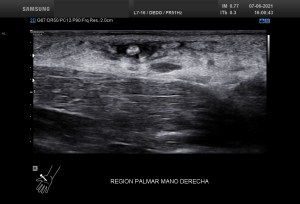

La imagen 3 y 4, como son tan nítidas, puedes ver como el quiste de Baker no es un quiste de Baker simple, la pared es grosera, tiene septos y ecoestrusturas que hacen pensar que el quiste ha podido sufrir algún sangrado. Hay que descartar la formación de lesiones sólidas o polos sólido en los quistes (usando doppler), por norma general, en todos aquellos quistes que estudiemos, en otras localizaciones, por ejemplo, en la mama, en el abdomen, etc.

Compara estos dos quistes de Baker, si los miras bien son prácticamente iguales. Hay una diferencia muy importante entre tanta igualdad…uno es normal, el otro es patológico. Las tres últimas imágenes, 5 a 7, corresponde a un quiste de Baker infantil, por tanto se considera un hallazgo que puede ser normal para estas edades, esta figura en a edad adulta es siempre patológica y en relación con artrosis y cambios degenerativos de la articulación.